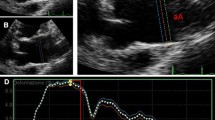

Local ascending aorta strain and distensibility

The local aortic strain (AA_Strain) was calculated from the systolic (Ss) and diastolic (Sd) areas of the aortic lumen at the level of the ascending aorta (AA_Strain = (Ss-Sd)/Sd). These lumen areas were measured from SSFP cine MR acquisitions using the automatic segmentation previously used on PC modulus images [30]. The Ss and Sd areas were defined as the maximum and the minimum of the curve describing the lumen area variation during the cardiac cycle (Figure 2).

According to the equation (2), the combination of the resulting strain with either the tonometric carotid pulse pressure or the brachial pulse pressure provided the ascending aorta distensibility indices, respectively named AA_Distc and AA_Distb.